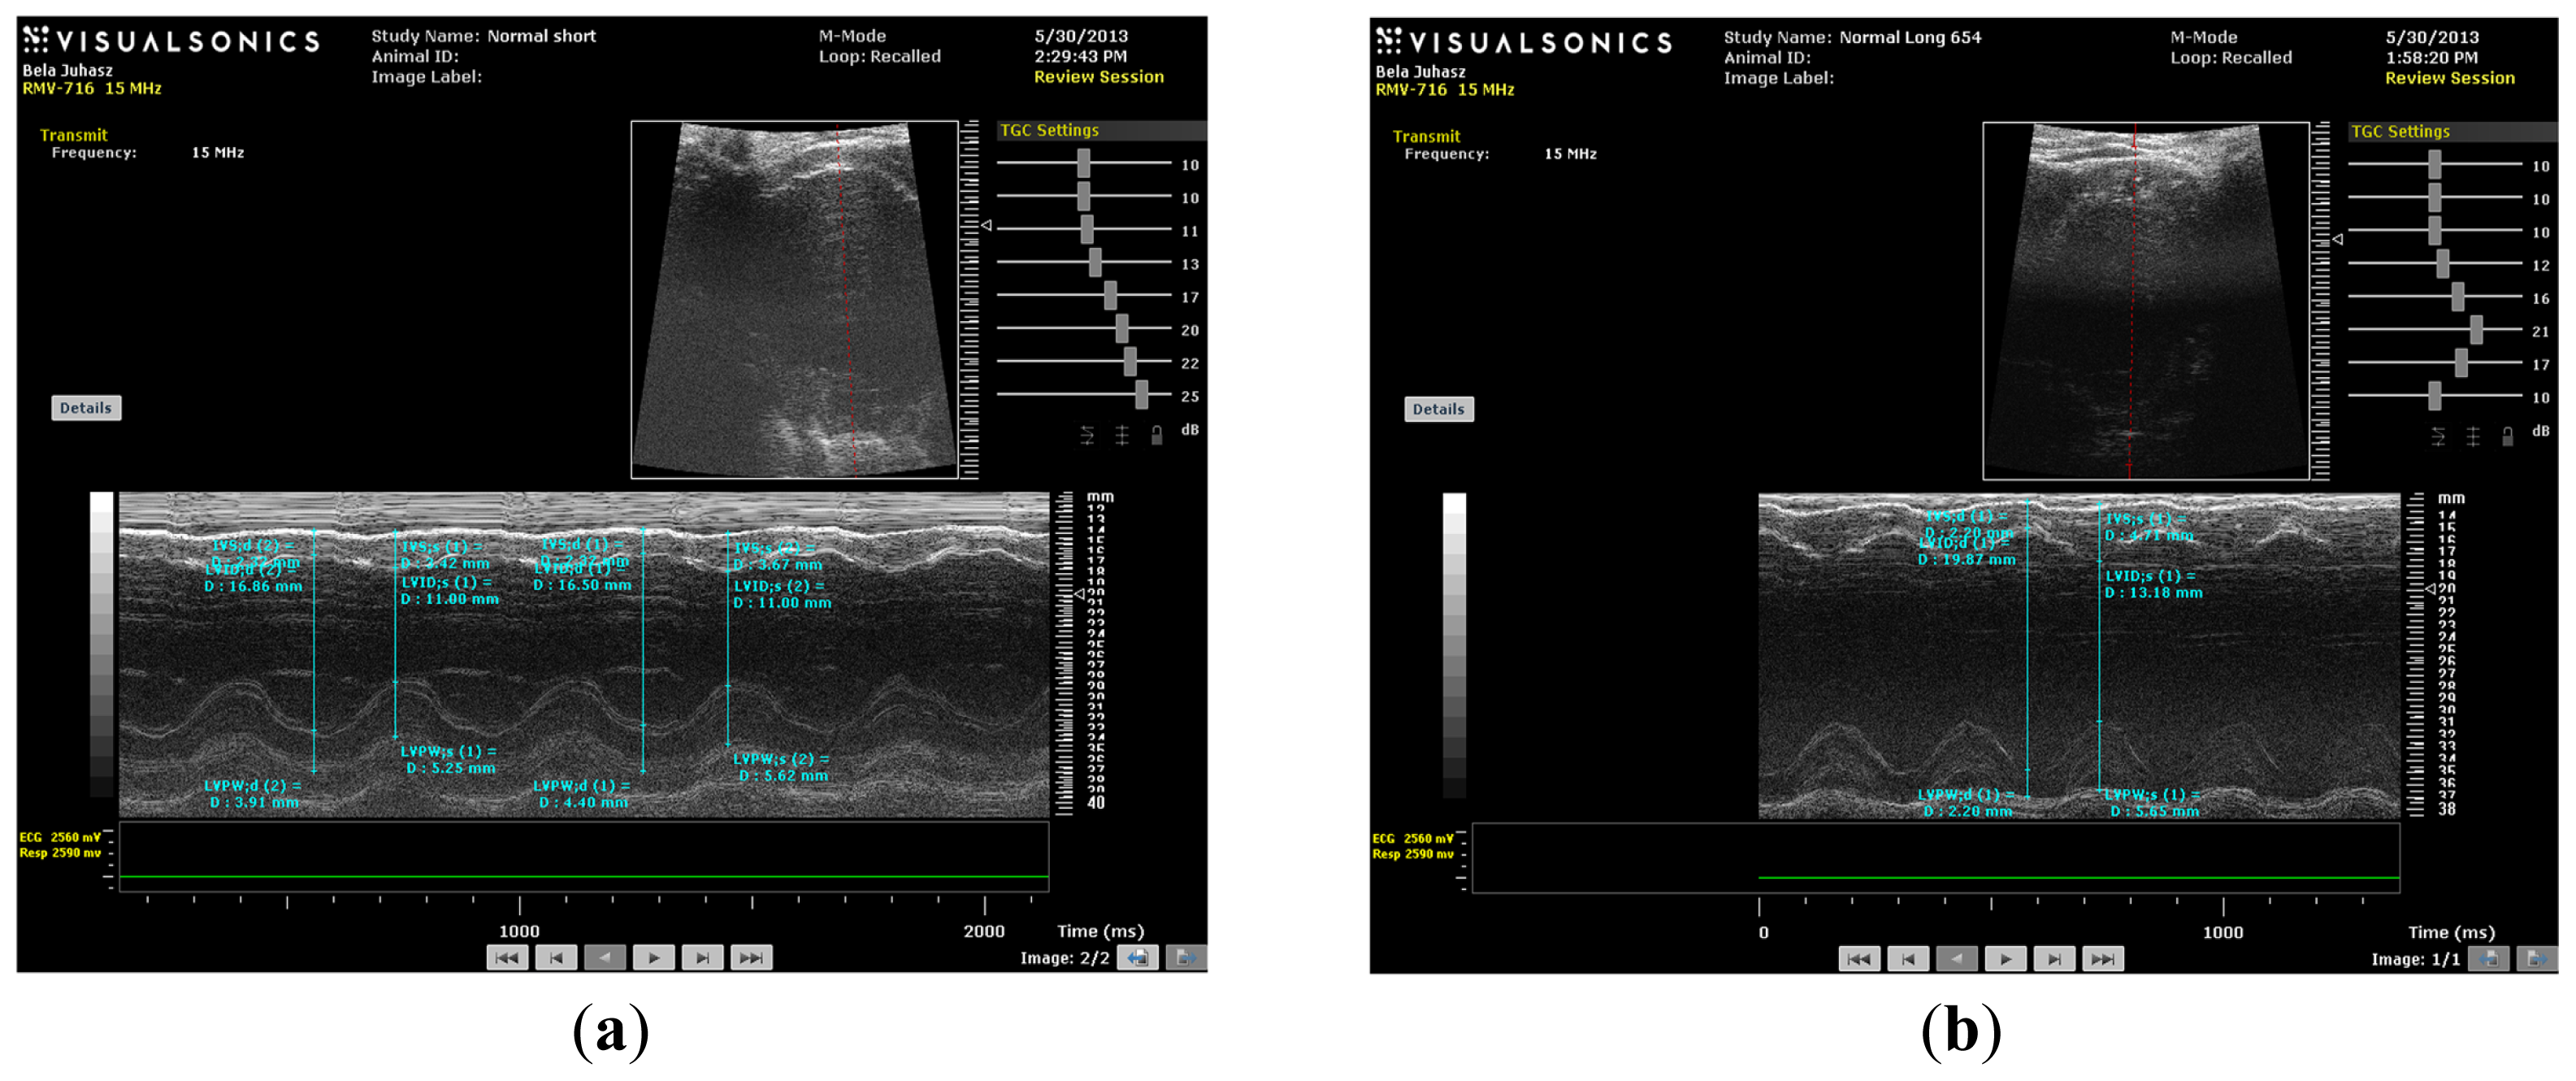

As shown in Figures 4 and 5, the values of fractional shortening (FS) and ejection fraction (EF) of the left ventricle were significantly reduced in HC long animals relative to their values in non-hypercholesterolemia control rabbits (p < 0.05) and to animals maintained for shorter time periods on hypercholesterolemia-inducing chow (HC short) (p < 0.05). These outcomes are expected based on previous studies, which reveal significant positive correlation between the occurrence of cardiac insufficiency and associated heart failure with possible left ventricular hypertrophy [22–24]. The aforementioned echocardiographic data provides insight into the influence of high cholesterol on the underlying pathogenesis of cardiovascular disease and helps account for other observations described in the present report, such as increased infarct magnitude in hypercholesterolemia animals. No significant differences in Groups I–III were observed. This expectation shows that neither ageing itself nor short-term hypercholesterolemia afflict the systolic and diastolic parameters and normal heart function. Although, in animals receiving a long-term cholesterol diet, these values were significantly lower (p < 0.05), which shows that long-term hypercholesterolemia can deteriorate left ventricle systolic function. As seen in Table 1, no significant differences in other echocardiographic parameters were measured. It should be also noted that the left ventricle (LV) masses of Groups II and IV were higher than the LV masses of the short-treated animals, although this only represents that the LV mass is correlated with increasing body weight, since these animals were five months older at the moment of extermination.

Figure 5.

(a) M-mode image of control short (CS) heart; (b) M-mode image of control long (CL) heart; (c) M-mode image of HC short (HCS) heart; (d) M-mode image of HC long (HCL) heart.

M-mode images demonstrate cross-sections of the heart swept by the instrumentation over a defined time period. This evaluation is conducted by placing the cursor line on 2D images at the mid-ventricular level, with the largest diameter in either the parasternal long or parasternal short axis view (on the M-mode pictures at the upper part 2D views with the cursor; at the lower part, the tracing at the cursor line could be seen). This technique, which provides a very high temporal resolution, allows the end systolic [minimal diameters, left ventricular internal diameter at end-systole (LVIDs)] and end diastolic [maximal diameter, left ventricular internal diameter at end-diastole (LVIDd)] diameters to be precisely measured. These parameters are used to calculate fractional shortening [(LVIDd − LVIDs)/LVIDd] and ejection fraction [(LVIDd − LVIDs)2/LVIDd2] (cubed formula), which are indicators of left ventricular emptying capacity. Normally, the heart ejects more than 50% of its end diastolic volume (ejection fraction), and the diameter shortens more than 25% (linear ejection fraction or fractional shortening). When the myocardial tissue is damaged (typically by oxidative stress), its contractile function is attenuated and emptying capability decreased.